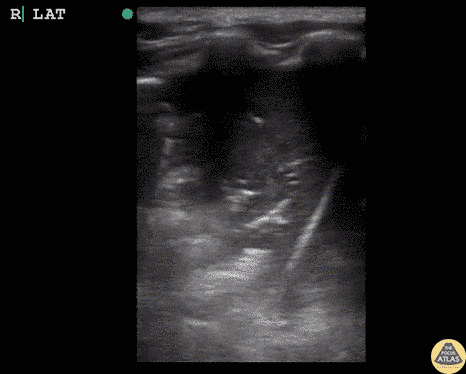

Pediatrics - Lung Hepatization (Pneumonia)

5 year old child with sickle cell disease. Coughing and fever for 3 days. On exam not ill appearing but decreased breath sounds over right lung. POCUS completed to evaluate for pneumonia. Hepatization of the lung clearly demonstrates consolidative process concerning for pneumonia. The beginning of the image demonstrates hepatization in the lung field. The ultrasonographer then slides the probe inferiorly over normal lung past the diaphragm to the liver, demonstrating how similar lung hepatization can appear compared to the actual liver. Dr. Sathya Subramaniam, Pediatric EM Fellow - Kings County/SUNY Downstate